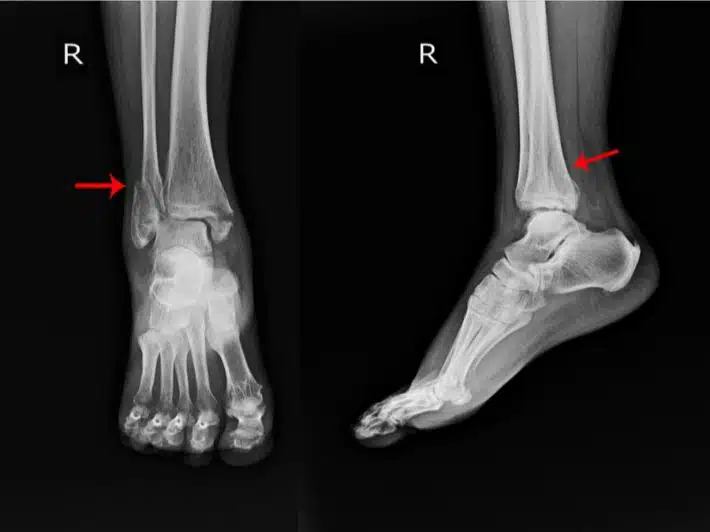

- الأشعة السينية: يخضع المريض في العادة إلى أشعة (x- ray) من أجل تحديد الصورة الهيكلية للعظم والتي مع سوء الالتئام قد تظهر في الأشعة على هيئة فراغات غير طبيعية.

- التصوير المقطعي المحوسب: يتم استخدام هذه الأشعة من أجل الحصول على تصور واضح للإصابة من الداخل من جميع الاتجاهات لتحديد المشكلة بشكل أوضح وبشكل أدق خاصة في حالة التئام الخاطئ.